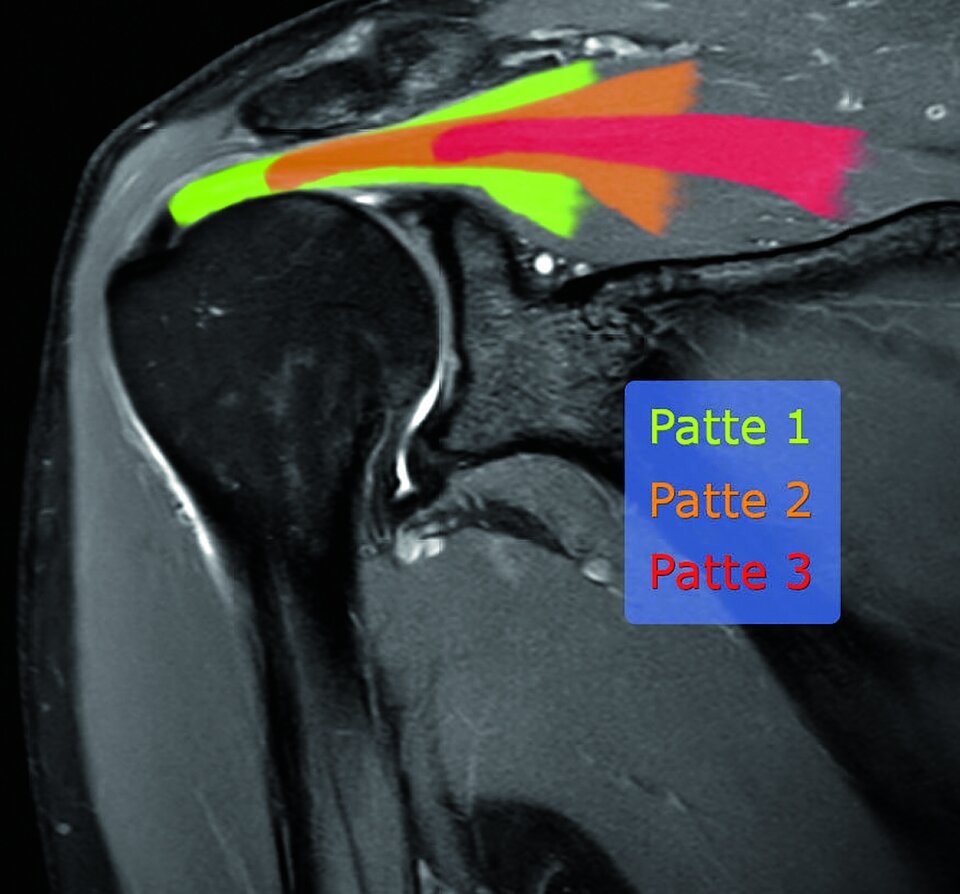

Diagnostisch steht eine MRT im Zentrum. Bewertet werden damit eine mögliche Verfettung des M. supraspinatus, eine Hypotrophierung, der Schweregrad einer sichtbaren Sehnenruptur und der Retraktionsgrad nach Patte.

Der Grad der Sehnenretraktion bei der Manschettenruptur wird nach Patte klassifiziert.

Der Grad der Sehnenretraktion bei der Manschettenruptur wird nach Patte klassifiziert. © wikimedia/ Hellerhoff